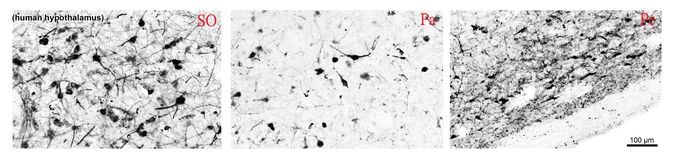

IHC-Fr analysis of immersion-fixed (4% PFA) human hypothalamus using GTX89578 Tyrosine Hydroxylase antibody, C-term.

IHC-Fr analysis of PFA-perfused human hypothalamic supraoptic (SO), paraventricular (Pa) and periventricular (Pe) nuclei using GTX89578 Tyrosine Hydroxylase antibody, C-term.

Antigen retrieval : citrate buffer pH 6 at 80C for 30min

Dilution : 0.1μg/ml